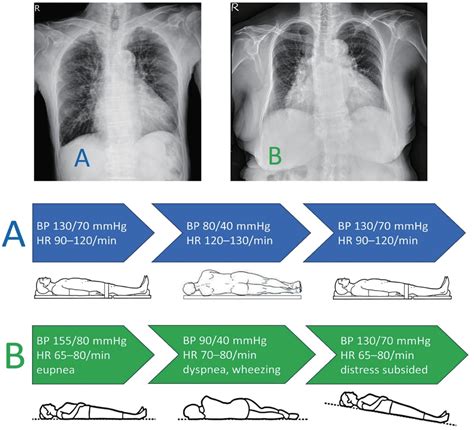

In the realm of medical procedures, patient positioning is a critical aspect that can significantly impact the outcome of various treatments. One such positioning technique that has gained prominence is the Left Lateral Decubitus Positioning. This method involves placing the patient on their left side with the body aligned in a way that facilitates specific medical interventions. This positioning is particularly useful in procedures such as colonoscopies, certain surgical interventions, and diagnostic imaging. Understanding the nuances of Left Lateral Decubitus Positioning is essential for healthcare professionals to ensure patient comfort, safety, and the effectiveness of the procedure.

The Left Lateral Decubitus Positioning is used in a variety of medical procedures. Some of the most common applications include:

• Surgical Interventions: It is used in surgical procedures that require access to the left side of the body, such as kidney surgeries and certain lung procedures.

• Diagnostic Imaging: This positioning is also used in diagnostic imaging procedures such as CT scans and MRIs to provide better visualization of the targeted area.